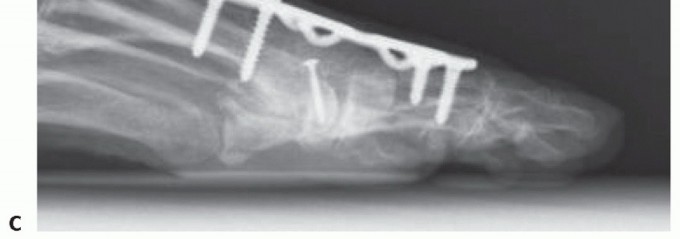

Implant is retained and conversion to total toe arthroplasty by placing matching proximal phalangeal metal component with polyethylene insert. If first-generation design, will need to exchange to HemiCAP DF to match the phalangeal and polyethylene component (FIG 11).

Implant removal and conversion to first MTP arthrodesis (FIG 12). Have freeze-dried allograft femoral head or iliac crest available. The author has had excellent results with intercalary allograft in the few instances where patients desired the implant to be removed due to pain. After implant removal and adequately preparing the joint, the approximate bone gap measured 2.0 to 2.5 cm. We have simply used a structural allograft (freeze-dried femoral head or iliac crest) cut to size and contoured using convex/concave reamer system to maintain hallux length on implant removal. In our experience, this has not been a complex procedure yet requires the appropriate graft and equipment for the case to flow smoothly.

FIG 12 • A. Patient developed arthrofibrosis and persistent pain despite proper implant alignment and no evidence of loosening. Elected for implant removal and conversion to fusion. B,C. Implant removed and intercalary allograft placed to maintain hallux length. Freeze-dried femoral head allograft used. Prepared with convex/concave reamers and stabilized with dorsal plate fixation. Solid bone fusion noted on AP and lateral radiographs. Weil osteotomy performed on second metatarsal and proximal interphalangeal (PIP) arthrodesis to address lateral transfer metatarsalgia and semirigid hammer toe deformity.